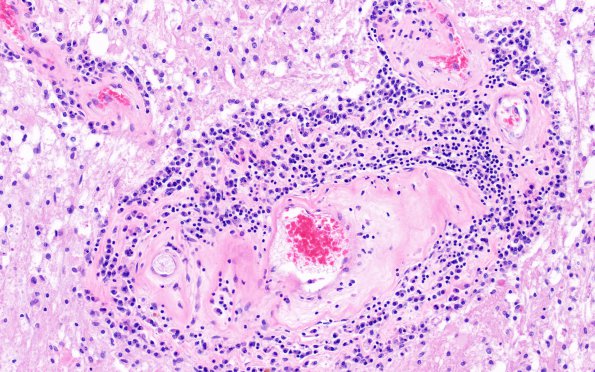

Washington University Experience | MYELIN (NON-IMMUNE MEDIATED) | Retinal Vasculopathy with Cerebral Leukoencephalopathy (RVCL, TREX1 Mutation) | 17D2 RVCL (Case 17) N4 20X

Most lesions are remote/inactive in histologic appearance; however, these developing lesions have parenchymal and perivascular infiltrate which are largely dominated by lymphocytes and an early histiocytic infiltrate.